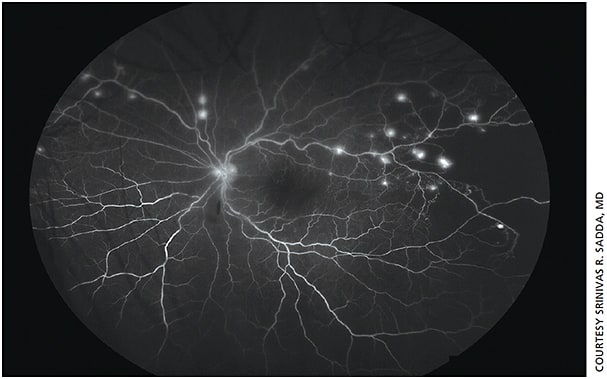

3. Evaluating for peripheral retinal vasculitis (Figure 2).

Figure 2. Widefield fluorescein angiogram of the left eye of a 25 y.o. Asian female who presented with shortness of breath and blurry vision. Some peripheral vessel staining as well as numerous small peripheral microaneurysms were seen. Right eye showed similar findings. Patient was ultimately diagnosed with Takayasu retinopathy.